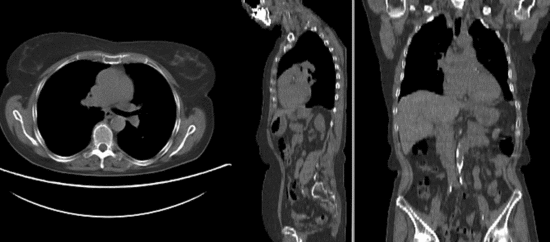

Discussion: Registration Challenges

• accuracy is the critical criterion here. We need the registration error (residual misalignment) to be smaller than the change we want to measure/detect. Agreement on what constitutes good alignment can therefore vary greatly.

• because of the large FOV we have strong non-rigid deformations from differences in patient/limb positions etc.

• images are large volumes (>100 MB total)

• the strong differences in head position is likely to distract the registration and lead to suboptimal results. Hence we produce a cropped version of the two CT images to calculate the BSpline transform.